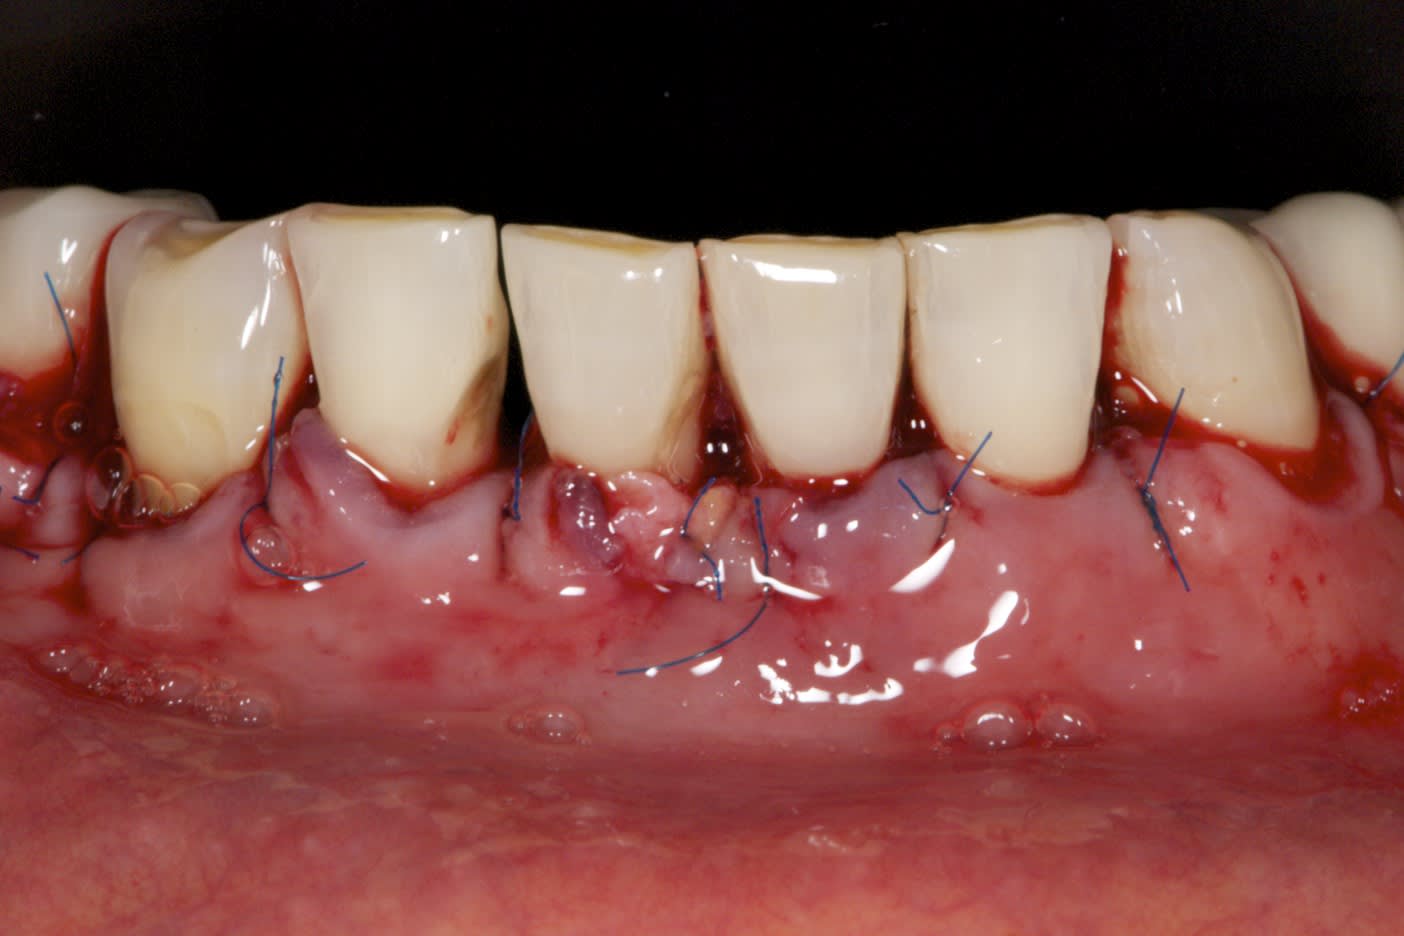

Résultat sympa à 14 jours

Sympas tes points suspendus au flow.

Joli les sutures, c est quoi comme fil?

Prolene 6-0